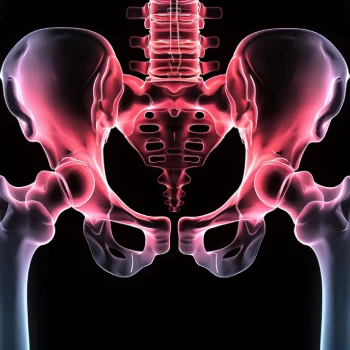

در این روش تصویر برداری یک صفحه (گیرنده یا دتکتور) در زیر عضو و قسمت مورد نظر قرار داده می شود و اشعه ایکس(دُز از اشعه جهت تشخیص) به همان قسمت که روی صفحه قرار گرفته تابنده می شود و توسط صفحه اطلاعات دریافت می شوند و همین اطلاعات پس از پردازش های لازم در نهایت عکس رادیولوژی به ما ارائه می دهد. کاربردهای رادیولوژی در منزل دقیقاً همان کاربرد رادیولوژی در بیمارستان ها می باشد از جمله بررسی انواع شکستگی ها، دررفتگی مفاصل، آرتروز مفاصل، دیدن پروتز های داخل استخوان از نظر بررسی موقعیت پروتز، آب آوردگی ریه(اِدم وافیوژن) و عفونت ریه، شکستگی دنده ها، انساد و وجود هوا در شکم و… می باشند. رادیولوژی در منزل تمام این خدمات را ارائه می دهد.

تصاویری از رادیولوژی در منزل توسط گاما پرتو